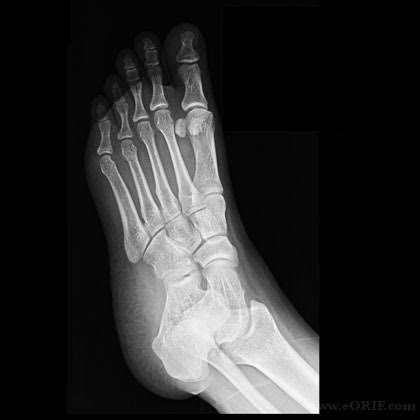

X-ray technology is used to examine many parts of the body.

Bones

- Fractures and infections. In most cases, fractures and infections in bones and teeth show up clearly on X-rays.

- Arthritis. X-rays of your joints can reveal evidence of arthritis. X-rays taken over the years can help your doctor determine if your arthritis is worsening.

- Osteoporosis. Special types of X-ray tests can measure the density of your bones.

- Bone cancer. X-rays can also reveal tumors in your bones.